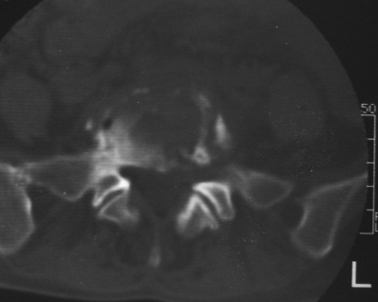

以下是引用dyqct在2007-3-1 18:04:00的发言:[br]腰5、骶1呈溶冰状骨质破坏,边界清楚,无明显硬化,内见多数沙粒状死骨,周围软组织肿胀。[br]考虑:腰5、骶1结核,建议严格抗结核治疗后复查。

以下是引用gaoxiao在2007-3-1 18:02:00的发言:[br]腰5骶1椎体见骨质破坏,其内见死骨形成,椎前软组织肿胀,感染性病变,腰骶椎tb。

以下是引用gaozhengyi在2007-3-1 19:39:00的发言:[br]骨质破坏并砂砾样死骨为椎体结核的表现。椎体结核骨质破坏区的特点是呈虫蚀状,常可见硬化缘。死骨表现为片状高密度影,正如本例。